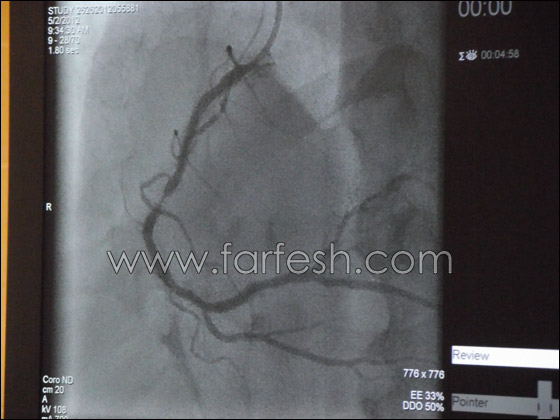

د.خالد سليمان (56 عاما)، من مدينة الناصرة، متخصص منذ 21 عاما في قسطرة القلب، وقد اجرى حتى الان ما لا يقل عن 25 الف عملية قسطرة، وكان قبل ذلك، قد تخصص في الامراض الباطنية في مستفى "هعيمك" في العفلوة، بعد ان تخرج من جامعة "بادوفا" في ايطاليا، ثم قرر خوض تخصص آخر هو القلب، وتحديدا القسطرة التي تفوق فيها عن سائر اقرانه من الاطباء الذين يعملون في هذا المجال.

خلال مسيرته الطبية والعملية اجرى د.خالد سليمان بعض الاستكمالات في جامعات هامبورغ الالمانية وميلانو الايطالية وبرع في مجال القسطرة عن طريق اليد حتى اصبح اليوم قادرا على ايجاد الحلول لكل المشاكل من خلال القسطرة من اليد، باستثناء تلك التي تحتاج الى ادخال اجهزة كبيرة، عن طريق الشريان فانه يضطر الى ادخالها عن طريق الفخذ وهي نادرة جدا.

شهد مجال عمليات القسطرة تطورات ونقلات نوعية كثيرة وسريعة اي في غضون فترة قصيرة نسبيا، ويقول د. سليمان "في العام 1989 كنا نجري قسطرة عادية معظمها لتشخيص الانسدادات في شرايين القلب وفي معظم الحالات كنا نرسل المرضى لاجراء عمليات القلب المفتوح، ومن ثم دخل عنصر البالون الذي استخدمناه لفتح او توسيع بعض الشرايين المسدودة جزئيا، وبعد سنوات قليلة ربما في العام 1994 دخلت الدعائم او ما يسمى (القوس) الذي يتم زرعه في شرايين القلب وتحديدا في النقاط التي يحدث فيها الانسداد". دخول هذه الدعائم الى طب القلب احدثت نقلة نوعية هامة جدا بعد ان كان العلاج في البالون غير مجديا في غالبية الحالات.

عملية ادخال الاقواس او الدعائم واستخدامها في فتح الشرايين خفضت بشكل ملحوظ عدد عمليات القلب المفتوح، وتزامنا او تعاقبا مع دخول هذه الدعائم تطورت ايضا انواع عديدة من الادوية التي تستخدم في عمليات القسطرة والتي تكون كفيلة بضمان فتح الشرايين لفترات طويلة، كذلك تطورت انواع من الدعائم في نهاية التسعينيات واصبحت هذه الدعائم مغلفة بانواع من الادوية التي تمنع تكاثر الخلايا في المنطقة التي يزرع فيها داخل الشريان، هذه الادوية تعمل على نفس المبدأ الذي تعمل عليه ادوية السرطان التي تحد من تكاثر الخلايا، وتمنع تكرار الجلطة او تكاثر الخلايا على الدعائم. في البداية كانت القسطرة تعالج شريان واحد، ولكن مع تطور هذا العلم اصبح بامكان الطبيب معالجة عدة شرايين في عملية قسطرة واحدة بضمنها الشرايين التاجية.

في معظم المستشفيات يتبعون لغاية اليوم عمليات القسطرة عن طريق شريان الفخذ، هذا الشريان كبير، يمكن من خلاله تمرير أي جهاز لإيصاله إلى شرايين القلب، لكن بالمقابل الأعراض الجانبية والمضاعفات المحتملة في القسطرة من الفخذ أكثر من المضاعفات المحتملة في القسطرة من اليد، وعند إجراء القسطرة عن طريق الفخذ يضطر المريض للبقاء مستلقيا لمدة 24 ساعة على الأقل، وهو معرض للنزيف في حالات معينة، خاصة لدى أولئك الذين يعانون من زيادة الوزن، والمسنين، ومرضى السكري، والأشخاص الذين يعانون من عدم تخثر الدم، وحتى العام 1998 كان د. خالد سليمان يجري عملية القسطرة من الفخذ، ولكنه تخصص بعد ذلك بالقسطرة عن طريق اليد، بدأها بالحالات البسيطة، حتى وصل اليوم إلى درجة عالية جدا من الكفاءة والمهنية، يستطيع من خلالها أن يحل أصعب المشاكل وأكثرها تعقيدا عن طريق القسطرة من اليد.

ما هي ميزات القسطرة عن طريق شريان كف اليد أو (المعصم)؟

يمكن من خلال القسطرة عن طريق اليد تجاوز كل المضاعفات المحتملة بالقسطرة عن طريق الفخذ، وأهمها يقول د. خالد سليمان إن المريض لا يضطر للبقاء في المستشفى، بل يتم تسريحه بعد ساعات قليلة من القسطرة حتى يتسنى له تناول بعض الأدوية الضرورية، كما أن احتمالات حدوث النزيف ضئيلة جدا ويمكن السيطرة عليها بسهولة لأن هذا الشريان يعتبر سطحيا ويمكن رؤيته ووقف النزيف فورا، في حين أن شريان الفخذ قد يسبب نزيفا داخليا أو نزيف في البطن.

ويقول د. سليمان انه يجري كل أنواع القسطرة، حتى أكثرها تعقيدا عن طريق اليد، إلا في حالات نادرة جدا يكون فيها مضطرا لإدخال أنبوب غليظ أو جهاز كبير نسبيا إلى القلب، فانه لا يدخل عن طريق شريان اليد الذي هو أضيق من شريان الفخذ، عندها فقط يقوم بإجراء القسطرة عن طريق الفخذ.

تجرى عملية القسطرة حيث يحدث تصلب في الشرايين وتكوّن الجلطة وانسدادها بشكل جزئي أو كلّي ومفاجئ، ولكن الحالة الأمثل لإجراء عملية القسطرة هي في حالة الإصابة بالنوبة القلبية، التي يكون فيها العامل الزمني مهم جدا لمنع حدوث ضرر في عضلة القلب، لذلك فإن المصاب بنوبة أو بجلطة، يصل مباشرة من سيارة الإسعاف إلى غرفة القسطرة، التي يعمل فيها اطباء مناوبون على مدار الساعة، ويتم على الفور فتح الشريان حيث حدثت الجلطة، ويتم اعادة جريان الدم لتقليل الضرر الذي قد يصيب عضلة القلب. وهنا يؤكد د. خالد سليمان ان كل دقيقة هي مهمة في هذه المرحلة. من جهة أخرى فإن هذا النوع من الجلطات المفاجئة قد يسبب السكتة القلبية، عندها ينبغي صعق المريض بالصدمة الكهربائية لإعادة تشغيل عضلة القلب ومن ثم نقله إلى المستشفى بأقصى سرعة.